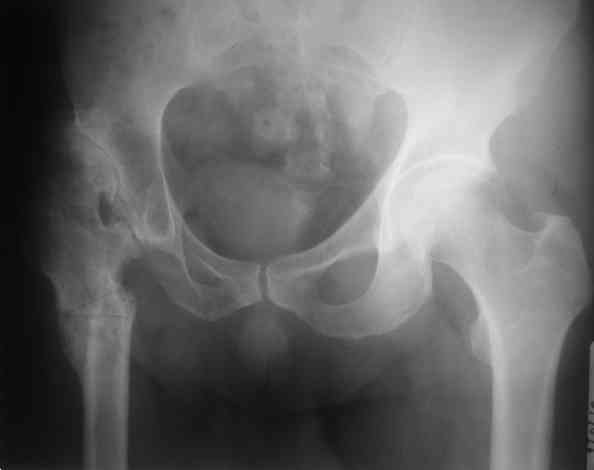

Уважаемый Андрей, ситуация не простая, нет обзорной Р-графии таза, поэтому сложно провести правильное планирование операции. Тем не менее, при планировании операции вертлужный компонент я бы установил в анатомическое положение. В отношении ножки - может быть два решения. Мое предпочтение - (операция типа Paavilaanen'a) поперечная остеотомия бедра на уровне чуть выше деформации, установка ножки Вагнера, скорее всего 190 мм, хотя возможно удастся обойтись и конической ножкой, это зависит от необходимой компенсации длины ноги. Продольная остеотомия б/вертела с последующей фиксацией к диафизу бедра с натяжением мышц. Есть и другой вариант - укорачивающая остеотомия в зоне деформации бедра с установкой ножки со стороны шейки. Мы делали и то и другое, первый вариант проще. В этой операции есть масса нюансов и нужно иметь опыт операций при дисплазии ТБС.

Уважаемые коллеги, без Р-граммы таза нельзя рекомендовать что-н.конкретно, представьте себе, что второй сустав находится в анатомическом положении,тогда позиция шейки протеза на оперируемой стороне будет примерно на уровне малого вертела, и тогда вам придется так укоротить б/вертел, что вы можете остаться без него.... Это очень не простые операции и нельзя без оценки всего таза что-н.советовать, во всяком случае мне так кажется

у пациента - эти проблемы с детства, потому по-нашему скромному опыту, лучше сохранить, некоторое укорочение, чтоб не произошел срыв компенсации, например на уровне позвоночника. Конечно же планировать нужно по нормальным снимкам.

Уважаемый Андрей! Действительно сложно спланировать операцию без обзорного снимка таза, а так же рентгенограмы бедра в аксиальной проекции. По поводу реконструкции бедренной кости могу предложить следующие варианты опробированные на практике (если есть необходимость пришлю Р-граммы).